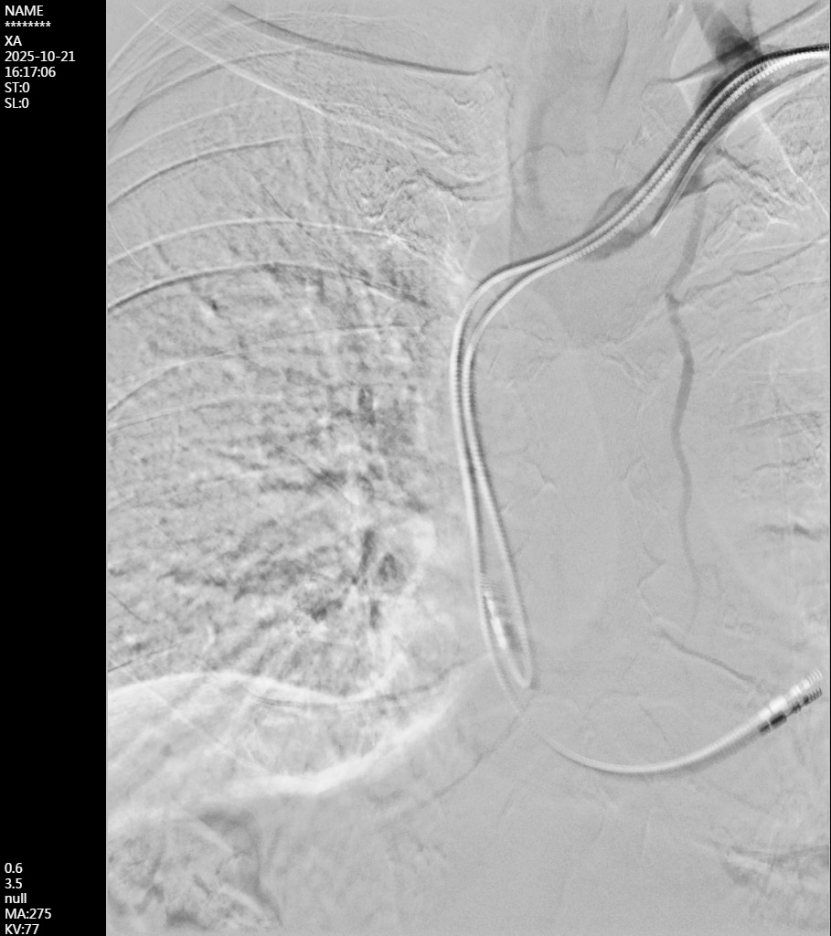

DSA显示左侧头臂静脉闭塞,侧支血管开放。

超高压球囊扩张中心静脉狭窄处,可见“蜂腰征”。